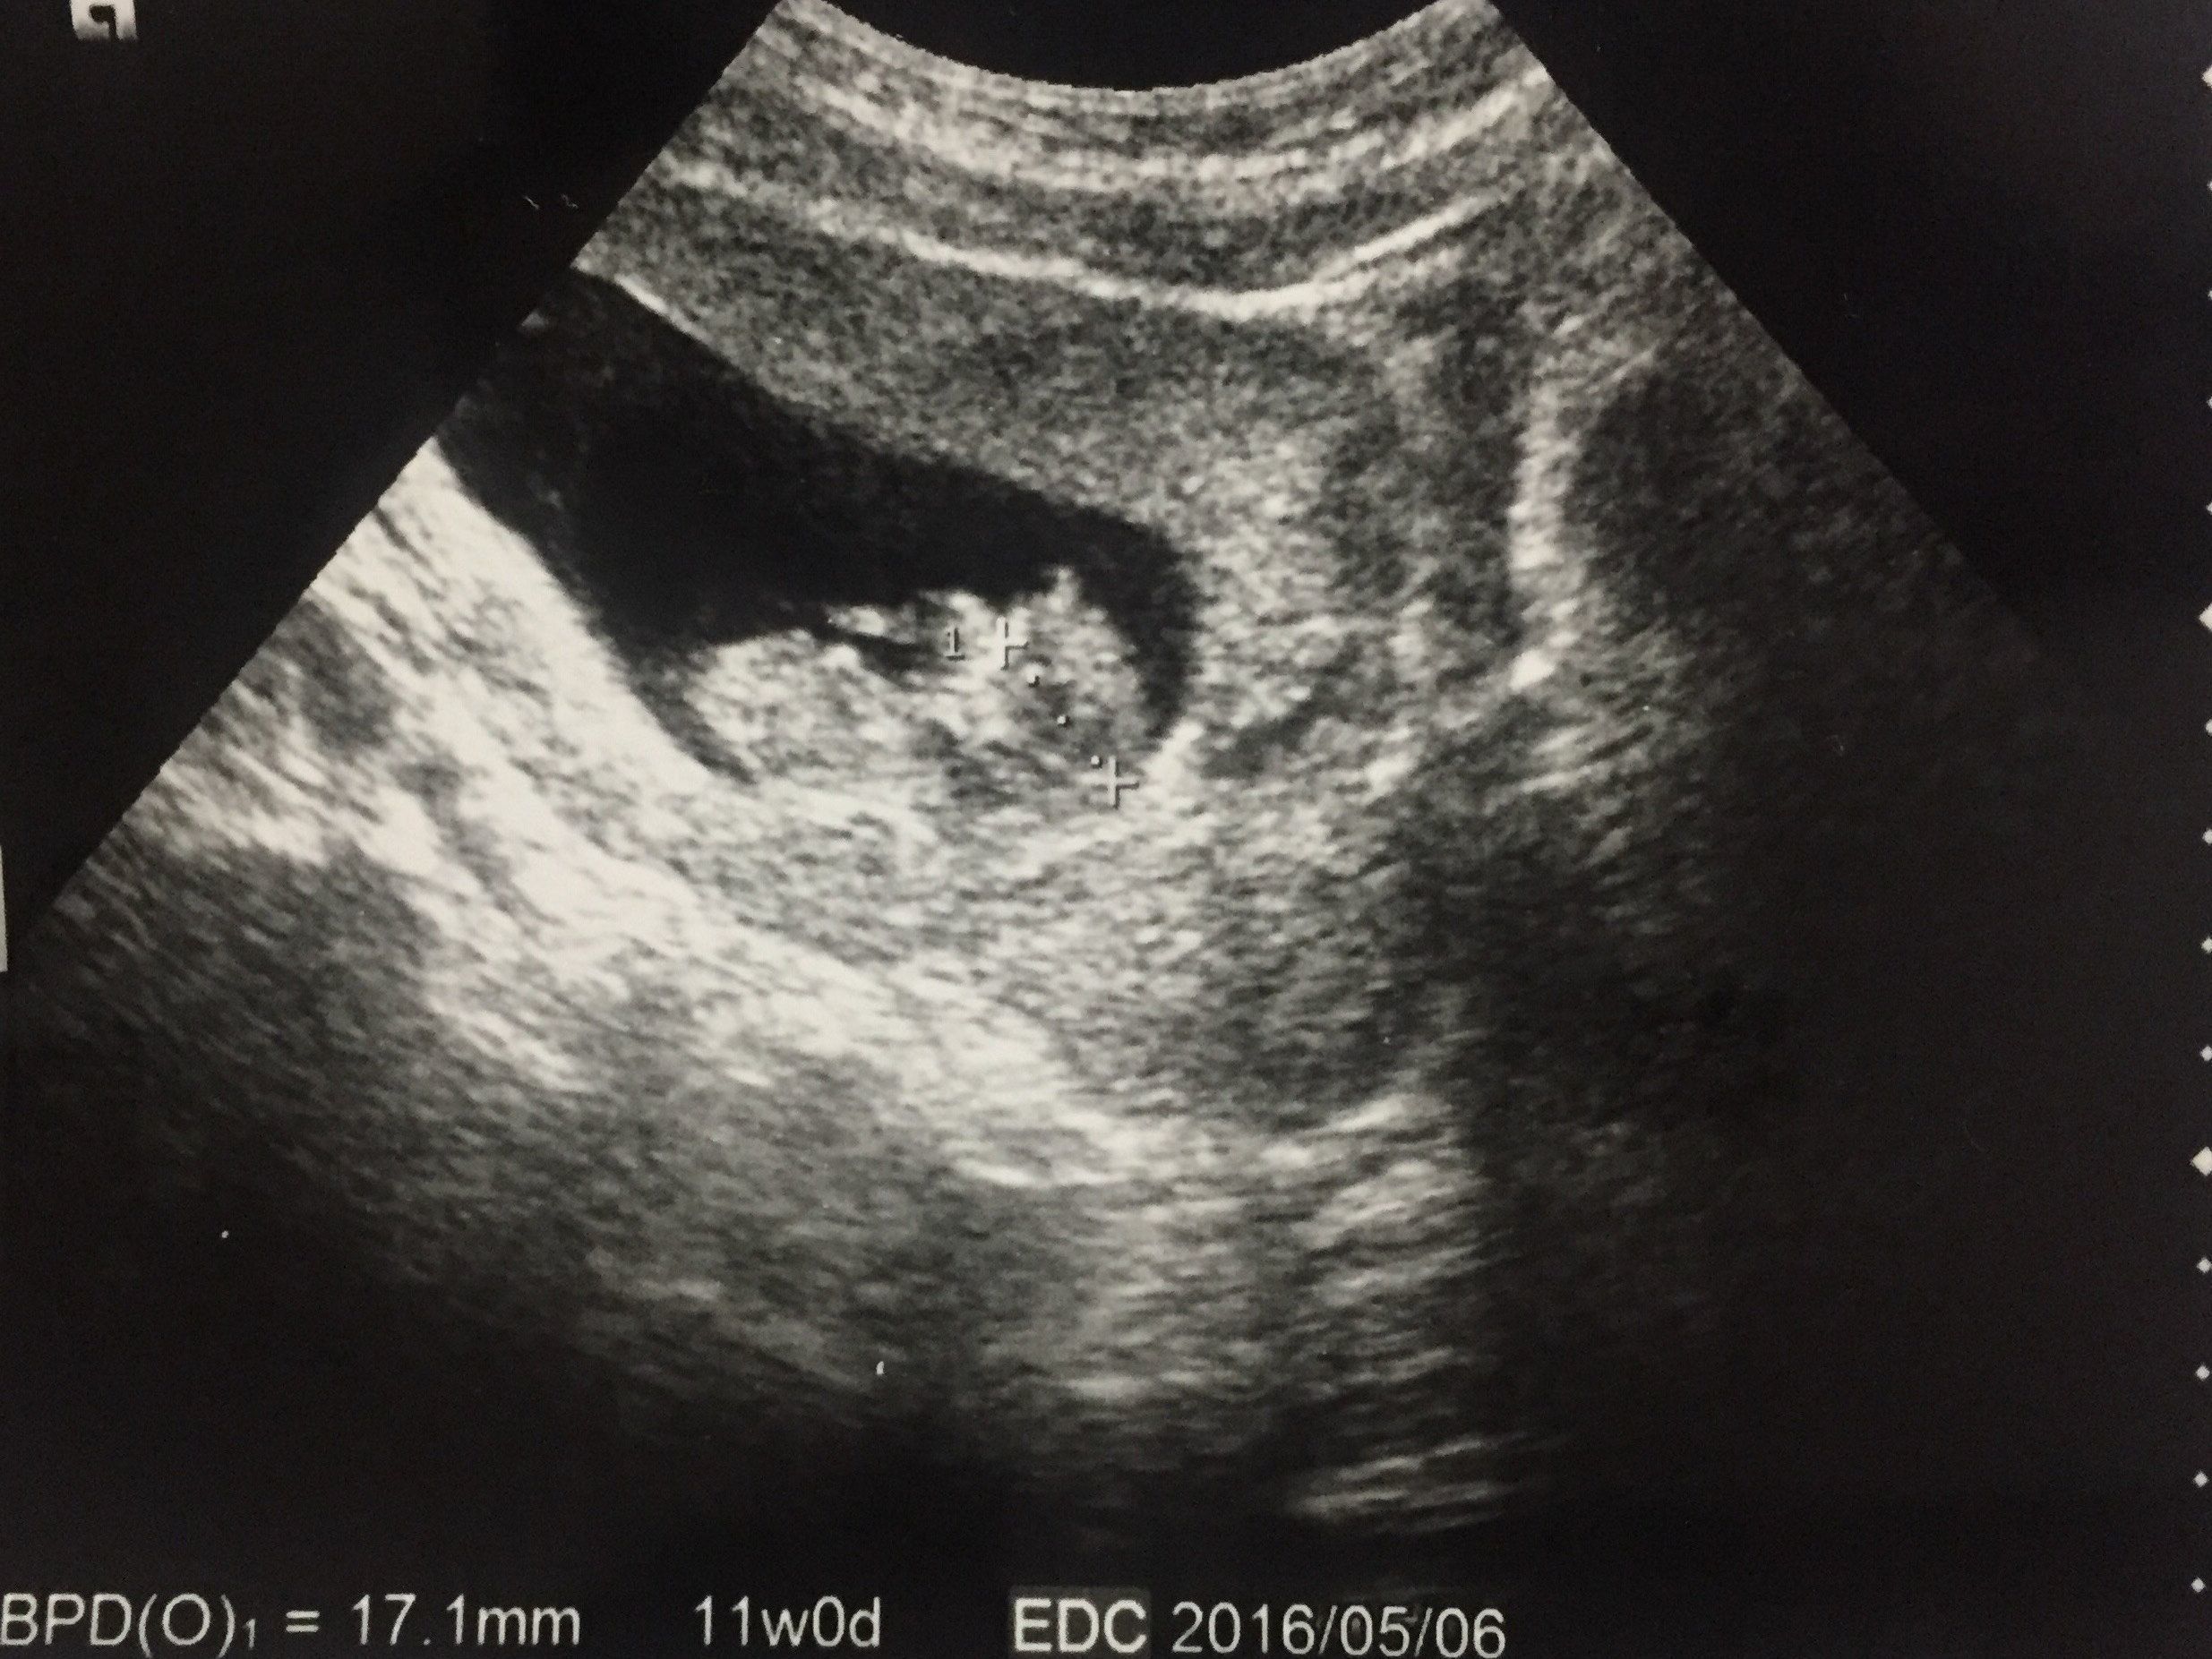

妊娠11週目 妊婦健診が楽しみな日々

エコー写真で赤ちゃんの体の形がはっきりわかるようになりました。この頃にはつわりもおさまり、日常生活も普通に送ることができました。しかし、妊婦健診が4週間に1回のペースになるので不安でした。おなかは大きくないし、胎動も感じられる時期ではありません。

「本当に、赤ちゃんはおなかの中で元気に育ってくれているのかな」と、次の健診を待ち遠しく思っていました。